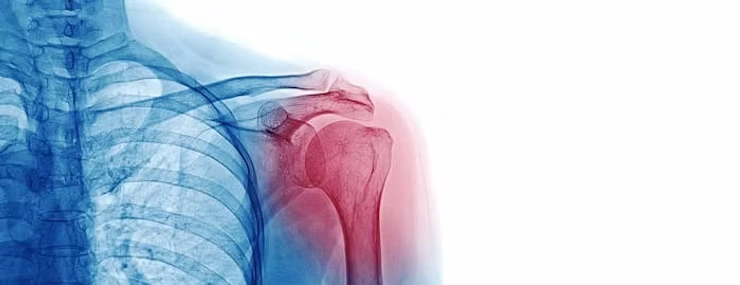

- A physiotherapist may however recommend additional diagnostic images such as x-rays, Diagnostic Ultrasound or Magnetic Resonance Imaging (MRI) if there appear to be any red flags or any other underlying condition.